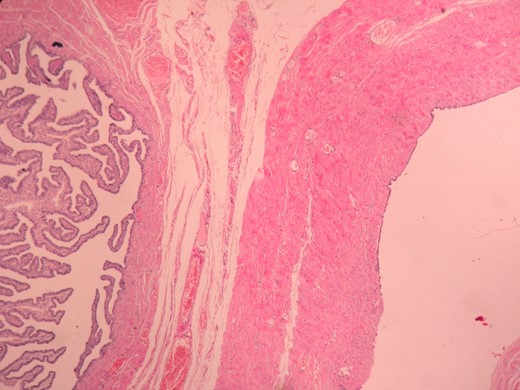

Definitive histopathological examination confirmed a paratubal cystadenoma of the right Fallopian tube (Fig. 3). The cystic mass involved the entirety of the right tube. The thick fibrocollagenized wall of the cystic mass, adjacent to the serosa of the tube, was lined with a single layer of ciliary columnar epithelium. Immunohistological examination revealed a p53-negative lining epithelium.

The thick fibrocollagenized wall of the cystic mass, lined with stratified and complex epithelium, H&E, ×200.

PTCs are generally asymptomatic, but they may rarely cause clinical conditions such as hemorrhage, torsion, rupture, infection or malignant transformation [7]. In 1909, the very earliest report of a pregnancy complicated by a PTC, described the excision of a torted PTC in an emergency setting. Histopathologically, PTCs are usually simple cysts. Neoplastic features of these cysts (i.e. cystadenomas) are so rare that they have previously been reported as individual case reports [8]. Differential diagnosis should include hydatid cysts of Morgagni and hydrosalpinx. Typically cystadenomas have a thick collagenized wall, and basically are lined with stratified and complex epithelium especially in focal areas [9]. PTCs are mostly 1–8 cm in diameter. It is emphasized that they may reach larger sizes under the influence of hormonal factors [7].